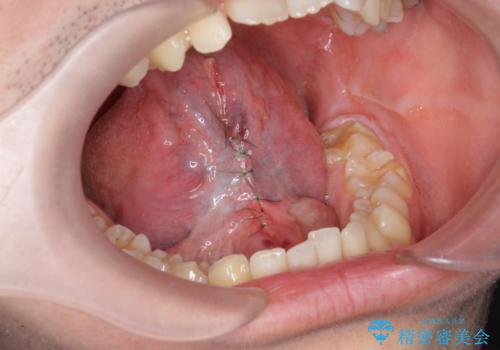

滑舌の改善 舌小帯の形成

静脈内鎮静下で、ほとんど記憶のないうちに手術を行い滑舌の改善を計画します。

舌小帯の形成を行うことで、動きがよくなり滑舌の改善を喜んでいただくことができました。

小手術に際して、少量の出血・疼痛のリスクがあります。

- 外科手術のため、術後に出血、痛みや腫れ、違和感を伴います